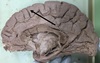

1. Identify 2 2. Identify 3 3. Identify 4 4. Identify 5 5. Identify 6

1. Falx Cerebri 2. Corpus callosum 3. Midbrain 4. cerebellum, grey matter 5. basilar artery

128

1. Name the dural venous sinuses related to number 2 2. Name the parts of number 3 3. Name the grey matter mass present in the white matter of structure 5

1. Superior and inferior saggital, straight sinus. 2. Rostrum, genu, trunk/body and spleenium 3. cerebellar nuclei

129

1. Identify 3 2. Identify 4 3. Identify 5 4. Identify 6 5. Identify 7 6. Identify 8 7. Identify 9 8. Identify 10 9. Identify 11 10. Identify 12

1. Dura Mater 2. Falx cerebri 3. Corpus callosum 4. Septum Pellucidum 5. Fornix (hippo to mamillary bodies) 6. Interthalmic adhesion 7. midbrain 8. Straight sinus 9. internal carotid 10. Tentorium cerebelli

130

1. Name the dural venous sinuses related to 4 2. Name the dural venous sinuses related to 12 3. How does 10 terminate

1. superior and inferior saggital, straight sinus 2. sigmoid, Transverse and superior petrosal sinuses 3. Great Vein of Galen